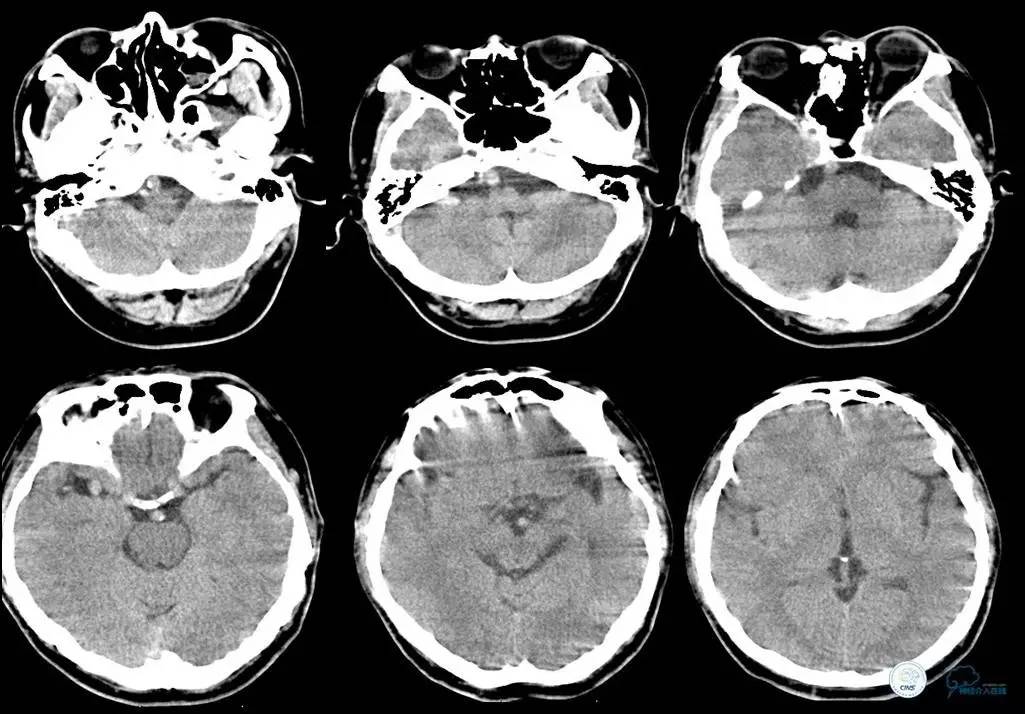

▼头CT

▼心电图:窦性心律,T波异常,心肌缺血改变。

血常规:白细胞为16.45×109/L,中性粒细胞为84.99%。

离子:钾为3.21mmol/L,镁为1.13mmol/L。

血糖:12.3mmol/L。

心肌酶:乳酸脱氢酶为187IU/L,肌钙蛋白、肌红蛋白、CK、CK-MB均正常。

凝血四项:凝血酶原时间为15.3s,活化部分凝血酶原时间为43.0s。

-

2014年12月15日22时50分

患者言语不清、右侧肢体麻木无力等症状缓解,但四肢末端厥冷。心电监护示,SPO2为99%,P为65次/分,R为18次/分,BP为103/60mmHg。T为35.5℃。

初步诊断为短暂性脑缺血发作。追问患者家属病史,入院前曾有大汗,未进食,低血容量性休克不除外。补液纠正休克。

2014年12月16日00时20分

患者精神差,全身不适,右肩背部疼痛,呕吐3次,呕吐物为胃内容物,排便2次,无黑便,四肢末端冰冷较前缓解。心电监护示,SPO2为93%,P为62次/分,R为18次/分,BP为101/55mmHg。T为36.2℃。急查心肌酶示CK、CK-MB正常。